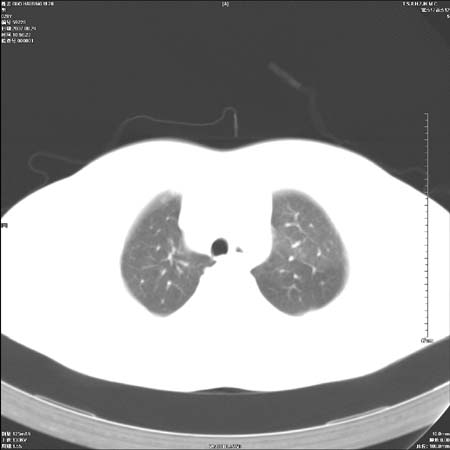

左肺门区软组织肿块,左肺上叶支气管开口消失,纵隔内见肿大淋巴结,考虑左中心型肺部,可以做纤支镜取病理确认.

支持左上叶中央型肺癌伴纵隔淋巴结转移.

左上叶中央型肺癌伴纵隔淋巴结转移

肿块形态影像支持左上叶中央型肺癌伴纵隔淋巴结转移。